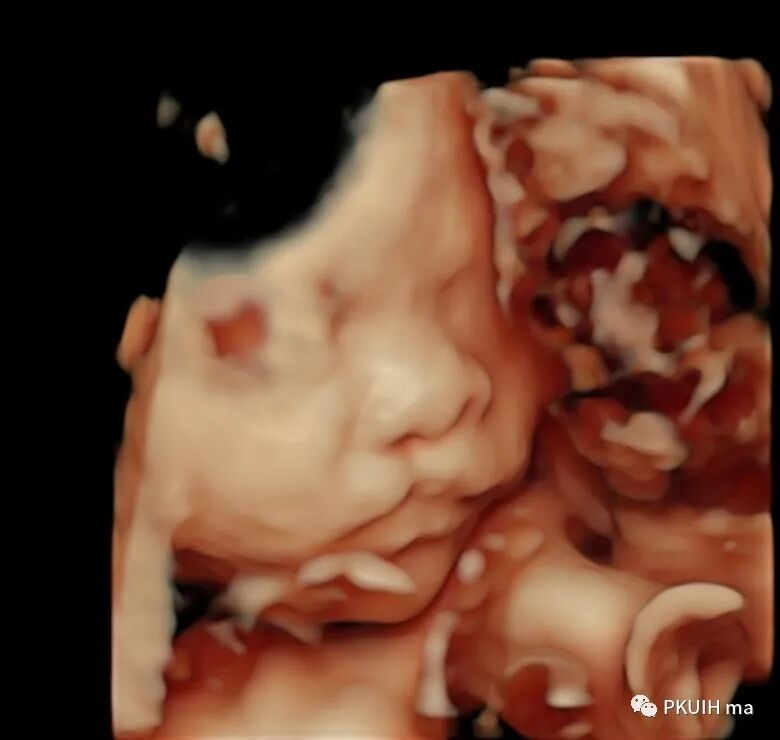

来看看这个胎儿,超声检查发现唇裂

大家觉得是几度?ⅡorⅢ度?(个人认为Ⅱ度

唇裂以上唇最为常见,下唇裂极为罕见。按裂的部位分为单侧和双侧,按裂的深度分为Ⅰ度(唇红裂)、Ⅱ度(未达鼻底)、Ⅲ度(整个上唇至鼻底完全裂开)。Ⅰ度、Ⅱ度为不完全唇裂,Ⅲ度唇裂为完全唇裂。

唇裂往往容易合并腭裂,单纯的唇裂大概占面裂的1/4,唇裂好发于男性胎儿、腭裂好发于女性胎儿。这个宝宝也是男孩,之前诊断的单纯腭裂都是女孩。

对于唇裂不建议分度,分度与治疗毫无任何关系,而唇裂(不管几度)预后非常好,千万不要因为唇裂而随意扼杀一个生命哦。在发现唇裂时要把重点放在有无合并腭裂,目前腭裂治疗技术也越来越成熟。记住唇红裂非常容易漏诊,所以唇裂诊断不可能达到100%。